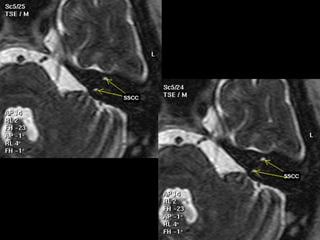

IAC MRI Anatomy and Search Pattern :

3D CISS sequence (thin axial high T2 sequences)

Finally:

Evaluate the following fluid filled

structures that are T2 bright:

•Semicircular canals

•Vestibule

•Ovoid in shape

•Cochlea

•Modiolus: hypointense area

at base